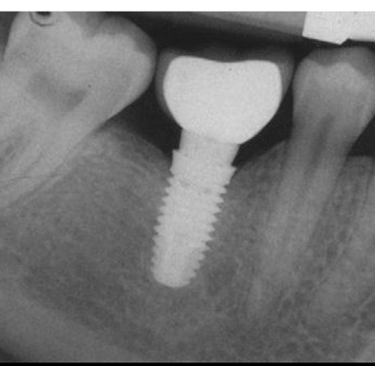

Wiele osób myśli o implancie jako o „nowym zębie”. To uproszczenie. Implant to niewielka, tytanowa śruba, która zastępuje korzeń zęba. Tytan jest materiałem biokompatybilnym, co oznacza, że organizm go nie odrzuca. Wręcz przeciwnie – zachodzi zjawisko osteointegracji, czyli trwałego zrośnięcia się metalu z kością szczęki lub żuchwy. Dzięki temu zyskujemy solidny fundament pod koronę protetyczną, która do złudzenia przypomina naturalny ząb.

Zanim dotkniemy skalpela, musimy wykonać zdjęcie pantomograficzne lub tomografię komputerową (CBCT). Na tym etapie oceniamy gęstość kości i odległość od ważnych struktur, takich jak zatoki szczękowe czy nerwy, oraz planujemy długość i grubość implantu, oraz kontakty z zębami przeciwstawnymi

To moment, w którym w znieczuleniu miejscowym umieszczamy tytanowy implant w kości. Zabieg trwa krótko i jest całkowicie bezbolesny. Po jego zakończeniu implant jest często niewidoczny w ustach, ponieważ zostaje przykryty dziąsłem na czas gojenia.

To najważniejszy etap, który trwa zazwyczaj od 3 do 6 miesięcy. W tym czasie kość dosłownie „obrasta” implant, czyniąc go integralną częścią Państwa ciała. W tym czasie pacjent może nosić uzupełnienie tymczasowe.

Gdy implant jest stabilny, odsłaniamy go i zakładamy tzw. śrubę gojącą, która kształtuje dziąsło. Po około 2 tygodniach lub skanujemy jamę ustną skanerem 3D, a technik wykonuje ostateczną koronę, którą cementujemy lub przykręcamy do implantu.

Co pewien czas wykonujemy kontrolne zdjęcie RTG, aby sprawdzić stan kości wokół implantu. To pozwala nam wykryć ewentualne zmiany, zanim zaczną dawać objawy bólowe.